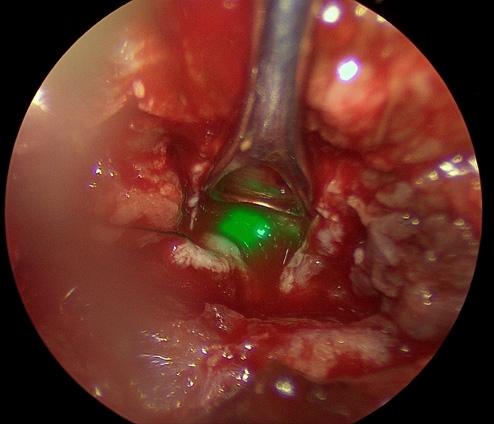

ICG 염색

형광 물질을 이용해 종양 조직과 주변 혈관 구조를 시각적으로 구분하고, 수술 중 판단과 절제 범위 설정을 돕는 기술입니다.

ICG 형광 염색은 수술 현미경과 함께 사용 시 종양과 정상 조직의 경계를 더 명확하게 확인하도록 돕고, 종양 주변 주요 혈관을 식별해 출혈 위험을 줄이며 절제 범위를 보다 정밀하게 설정하는 데 도움을 줄 수 있습니다.

정상 뇌 조직과 종양 경계가 모호한 경우, 정확한 절제와 기능 보존을 함께 고려한 수술 계획에 유용합니다.

ICG 염색 수술 이미지

수술 이미지

ICG 형광 확인 이미지

형광 확인